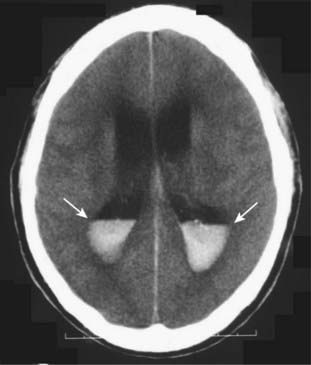

image

Figure 25-11 Intraventricular hemorrhage.

Intraventricular hemorrhage (solid white arrows) is common in premature infants but less common in adults. It usually results from break-through bleeding from a brain contusion or subarachnoid hemorrhage and requires a considerable amount of force to produce. Therefore, it is typically associated with severe brain damage and has a poor prognosis.